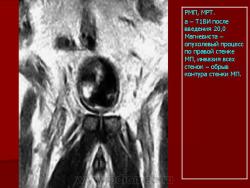

В случае прорастания опухолью всех слоев стенки мочевого пузыря при эндовезикальном сканировании четкая структура мышечной стенки отсутствует (Рис. 6), а опухолевая ткань распространяется на паравезикальную жировую клетчатку (стадия Т3).

Эндовезикальное сканирование позволяет выявить распространение опухоли на интрамуральный отдел мочеточника (Рис.7) и предстательную железу (стадия Т4). Однако следует отметить, что при инвазии опухоли в предстательную железу более информативным является трансректальное сканирование. Что касается распространения опухоли на другие органы и ткани (брюшина, кости таза, тонкий кишечник и прямая кишка), то возможности эндовезикального исследования здесь ограничены. В подобных случаях значительную помощь в диагностике оказывает компьютерная томография. То же самое можно сказать и о диагностике метастатического поражения регионарных лимфатических узлов.